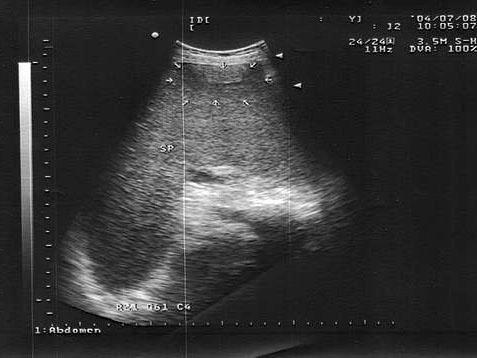

问题 男,18岁,外伤1小时就诊。结合超声声像图,诊断为?(?)

选项 A.脾外伤血肿 B.脾淋巴管瘤 C.膈下积液 D.脾皮样囊肿 E.脾血管瘤

答案 A